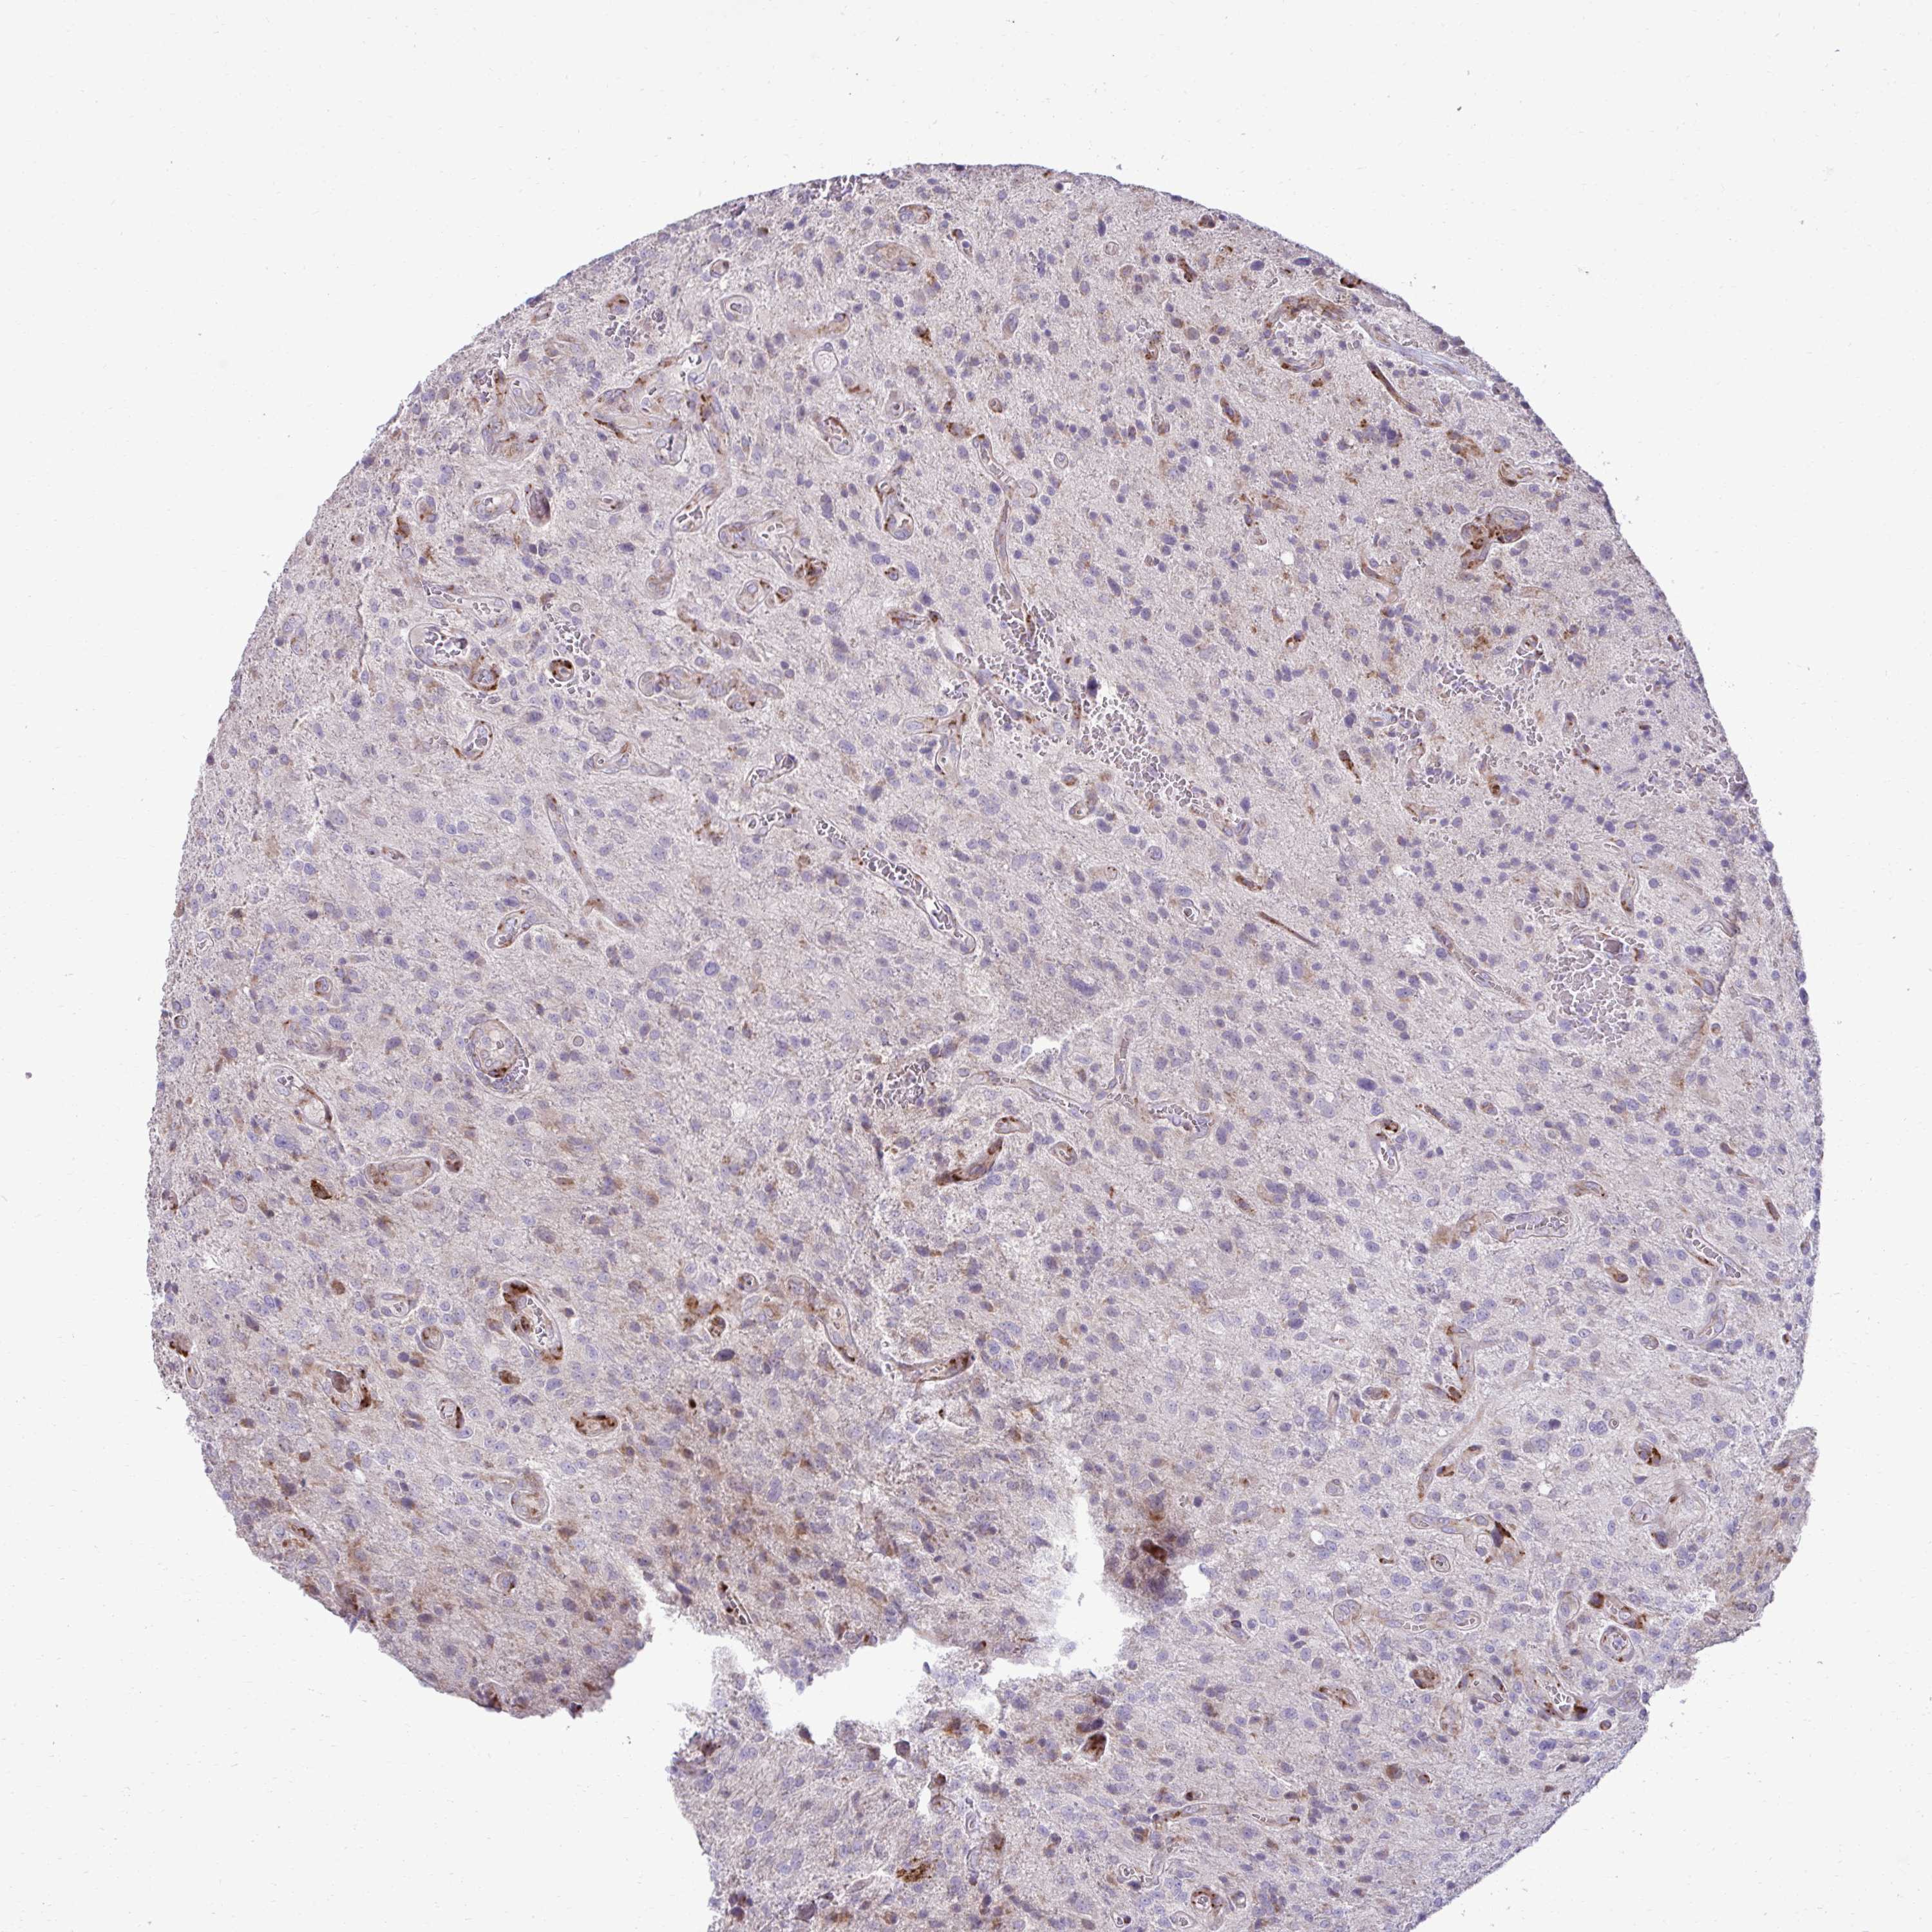

GLIOMA - Protein expressioni

A mouse-over function shows sample information and annotation data. Click on an image to view it in a full screen mode. Samples can be filtered based on level of antibody staining by selecting one or several of the following categories: high, medium, low and not detected. The assay and annotation is described here.

Note that samples used for immunohistochemistry by the Human Protein Atlas do not correspond to samples in the TCGA dataset.

Antibody stainingi

Antibody staining in the annotated cell types in the current human tissue is reported as not detected, low, medium, or high, based on conventional immunohistochemistry profiling in selected tissues. This score is based on the combination of the staining intensity and fraction of stained cells.

Each image is clickable and will lead to virtual microscopy that enables deeper exploration of all samples and also displays staining intensity scores, fraction scores and subcellular localization as well as patient and tissue information for each sample.

Antibody HPA058455

Antibody HPA061230

Staining

High

Medium

Low

Not detected

Intensity

Strong

Moderate

Weak

Negative

Quantity

>75%

75%-25%

<25%

None

Location

Nuclear

Cytoplasmic/membranous

Cytoplasmic/membranous,nuclear

Glioma, malignant, Low grade

Glioma, malignant, High grade